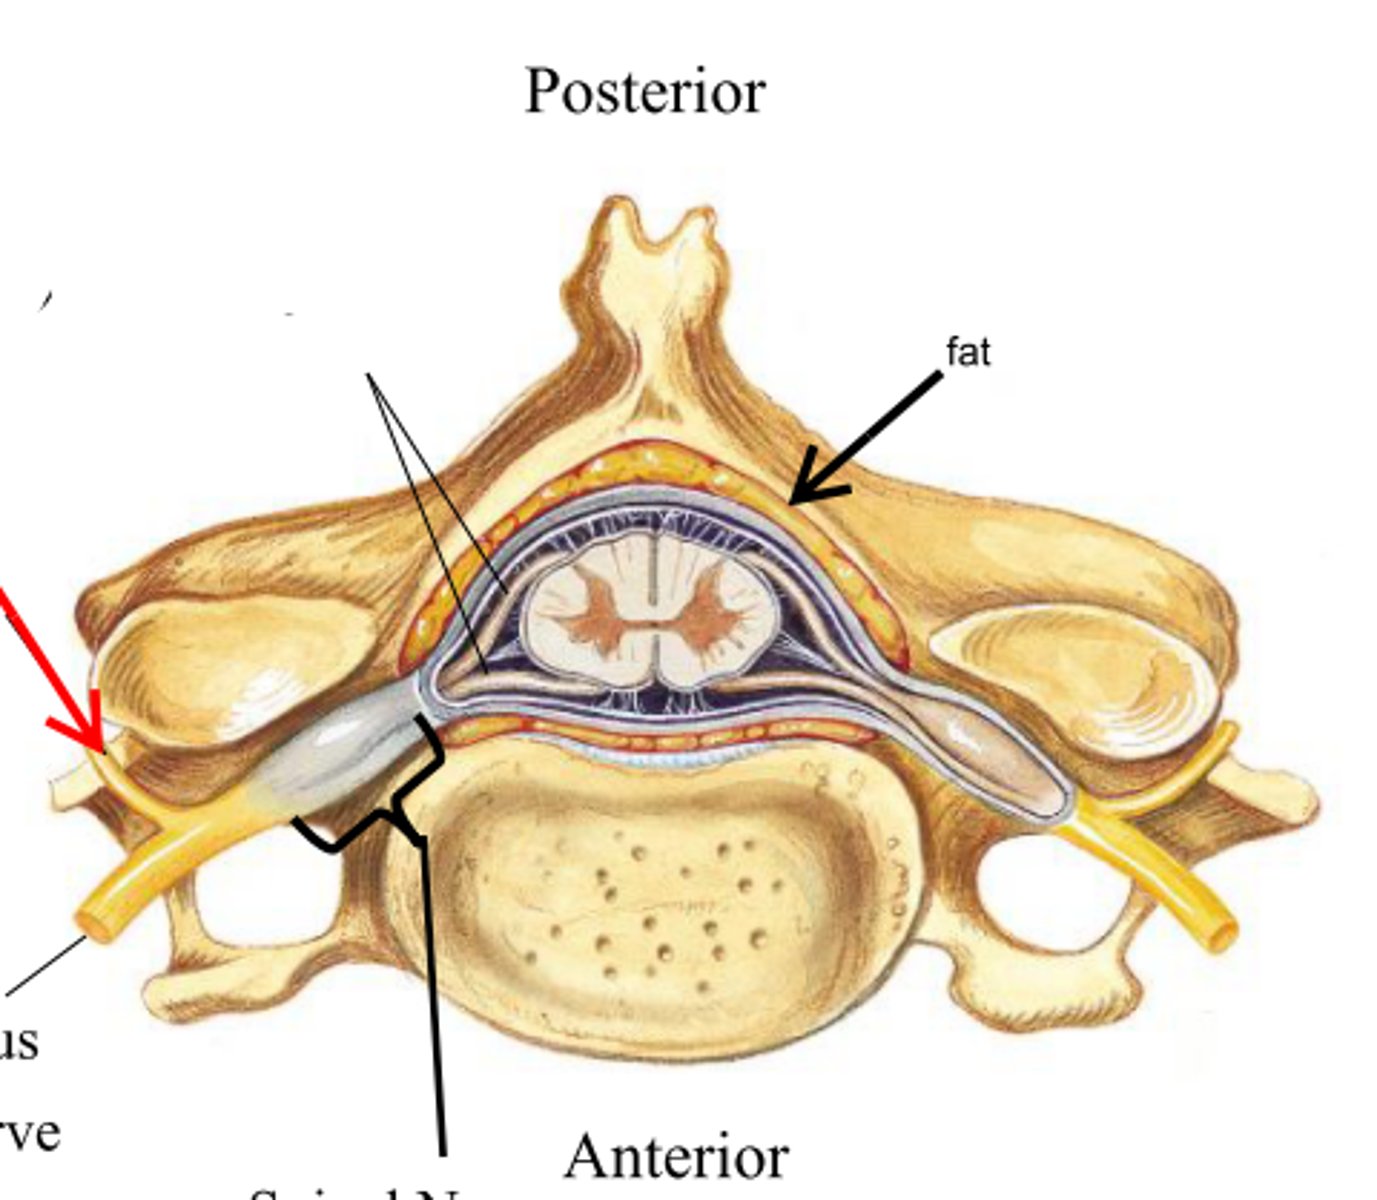

spinal cord

31 pairs of nerves arising from the spinal cord; letter abbreviation for region of spine they originate from; forms where the anterior and posterior roots join; mixed nerves (contain sensory and motor fibers)

posterior (dorsal) rootlets

merge to form a root

posterior (dorsal) root

contains sensory axons

posterior (dorsal) root ganglion

contains cell bodies of sensory neurons

true spinal nerve

anterior root

contains motor axons

spinal meninges

dura mater, arachnoid mater, pia mater (PAD to protect the spinal cord from deep to superficial)

dura mater (spinal cord)

thick, outermost layer of the meninges; 5 on image

arachnoid mater (spinal cord)

middle weblike layer of the meninges; 4 on image

pia mater (spinal cord)

thin, delicate inner membrane of the meninges; 3 on image

central canal of spinal cord

center of spinal cord which contains cerebrospinal fluid

posterior median sulcus

a shallow vertical groove dividing the spinal cord throughout its whole length in the midline posteriorly.

anterior median fissure

a groove along the anterior midline of the spinal cord that incompletely divides it into symmetrical halves

gray matter of the spinal cord

cell bodies, dendrites, and unmyelinated axons arranges in a butterfly shape with anterior and posterior "horns"

posterior (dorsal) horns

contain axons of sensory neurons and cell bodies (sensory nuclei) of interneurons